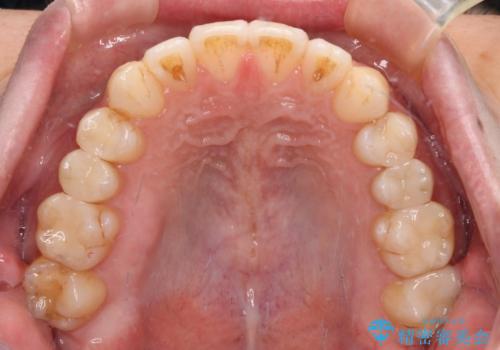

オープンバイトと目立つ銀歯 インビザライン矯正とセラミック修復治療

- 奥歯の目立つ銀歯と上下前歯の叢生と隙間を気にして来院された患者様です。

開咬の治療は、前歯を閉じるように動かすとともに、上下臼歯を圧下(骨内にめり込ませる)させることで進めて行きます。

インビザラインは臼歯の圧下を効果的に行えるため、インビザラインを用いて矯正治療を行うこととしました。

銀歯については、矯正治療により咬合関係を改善し、矯正治療後半に修復治療を行うこととしました。

修復治療後に細かい部分をインビザラインで再度仕上げるプランとしました。